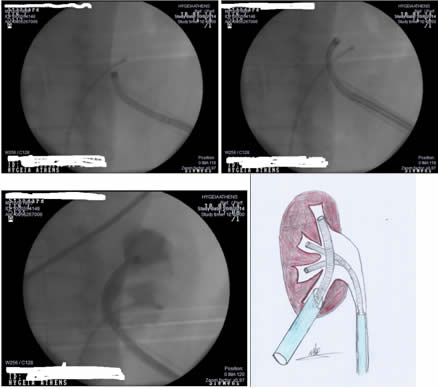

Εδώ δημιουργείται ένας δρόμος από το δέρμα προς το νεφρό του ασθενούς ενώ ταυτόχρονα ένα άλλο ενδοσκόπιο ανέρχεται από την κύστη προς τον νεφρό.

Εντός του νεφρού τα δύο ενδοσκόπια συνεργάζονται και προσεγγίζεται κάθε λίθος όσο μεγάλος και να είναι σε κάθε σημείο όσο δυσπρόσιτο και να είναι αυτό.

Αυτή η δυνατότητα είναι πολύ σημαντική σε περιπτώσεις με λίθους σε κάθε σημείο του νεφρού όπως στην φωτογραφία.

Η μέθοδος είναι ότι καλύτερο έχει να προσφέρει η σύγχρονη ουρολογία στη πάθηση της νεφρολιθίασης. Εφαρμόζεται από εξαιρετικά εξειδικευμένους χειρουργούς και απαιτεί κατάλληλο τεχνολογικό εξοπλισμό και τεχνογνωσία.